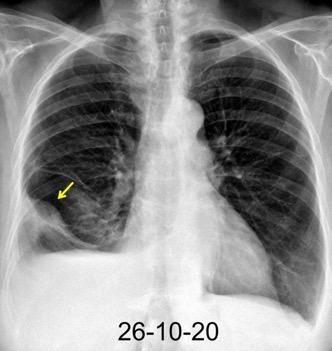

Tromboembolismo pulmonar.

Frecuencia del derrame:

Rx: 32%. TC: 47%

Unilateral. 85%

< 1/3 del hemitórax: 90%

Todos exudados

58% con eritrocitos

21% tabicación lo que causa demora en el diagnóstico

TEP. Empiema pleural. Atelectasia redonda

Porcel JM et al. Analysis of pleural effusions in acute pulmonary embolism: radiological and pleural fluid data from 230 patients. Respirology 2007/ Iguchi T et al. Desquamation of the subpleural lung parenchyma caused by empyema after pulmonary embolism: A case report. Respirol Case Rep. 2022 .